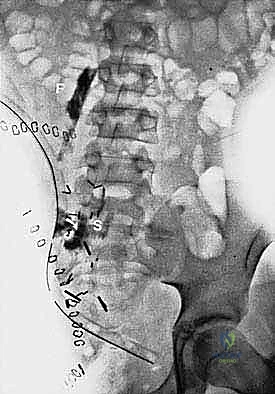

التصوير بالرنين المغناطيسي (MRI): هو المعيار الذهبي لتحديد حجم الورم بدقة، وامتداده في الأنسجة الرخوة، وعلاقته بالأوعية الدموية والأعصاب.

التصوير المقطعي المحوسب (CT Scan): يُستخدم لتقييم مدى تدمير العظام وتخطيط أماكن القص العظمي (Osteotomy) أثناء الجراحة.

الخطوة الرابعة: قص العظام (Osteotomy) وفصل الحوض

باستخدام مناشير عظمية متقدمة، يتم فصل عظام الحوض عن العمود الفقري (عند المفصل العجزي الحرقفي) وفصلها من الأمام (عند الارتفاق العاني). يتطلب هذا دقة متناهية لضمان استئصال الورم بالكامل دون المساس بالأعضاء الداخلية في الحوض (مثل المثانة والمستقيم).